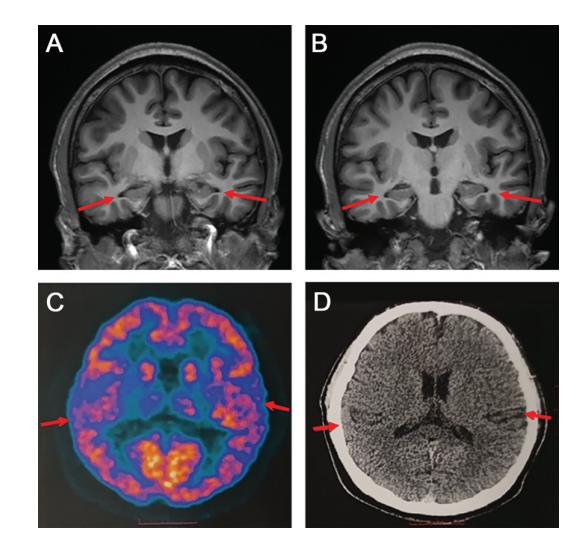

贾龙飞介绍,PET扫描和脑脊液指标检查,以及多种量表检测可以相辅相成,互相印证,以此才可以做出准确的临床诊断。

图源:首都医科大学宣武医院研究小组对此病例的诊断为“疑似AD”,原因是仍有部分评估结果不符合AD的国际公认诊断标准(NIA-AA)。此外,该文章也提出了此项研究的局限性,由于患者比较年轻,不能接受大脑活检,需要长期随访进一步支持该团队的诊断。